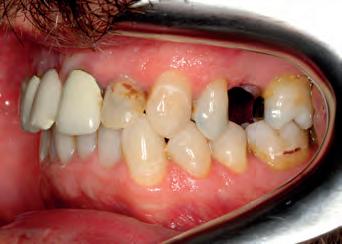

TOP ROW: Before lower occlusal, Before retracted in occlusion 2ND ROW: Before retracted left in occlusion, Before retracted left open 3RD ROW: Before retracted open, Before retracted right in occlusion 4TH ROW: Before retracted right open, Before upper occlusal